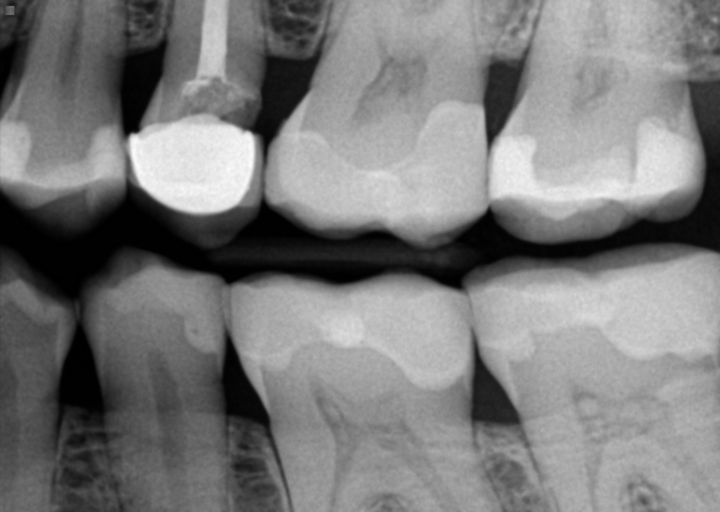

Yes I would like to no if there is any none loss in my X-rays .If So will you please let me no how much bone loss do you see.I would like to no because my crowns have started shaking a little. Thanks Jackie

Unfortunately, your xray did not come through.  In order for bone loss to be diagnosed, bitewing xrays along with peridontal chartinging will be used to assess the amount of bone loss you have.  These readings will also be monitored each year during your periodic oral evaluation after your hygiene appointment.  It is imperative to stay on top of your hygiene appointments if you have bone loss.  Bone will not come back once it is lost and when there is not sufficient bone to hold the teeth, they can become loose or must be removed.